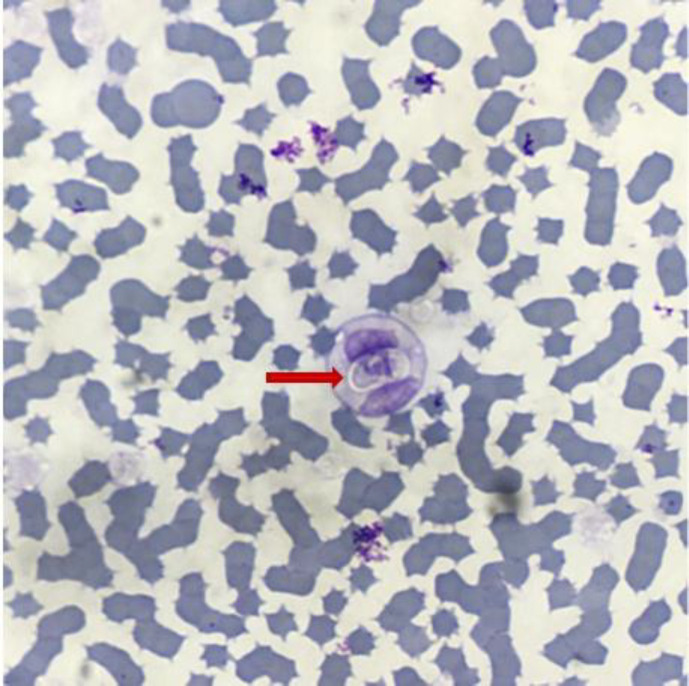

A 6-year-old male domestic short-haired cat (Felis catus) was presented with weakness, anorexia, fever, icterus, a painful abdomen, ruffled hair and a tick infestation, and it had no prior surgery. Laboratory analysis revealed left-shifted neutrophils, thrombocytopenia, low albumin content and high serum bilirubin concentration as well as activities of hepatic enzymes including alanine aminotransferase and aspartate aminotransferase. Azotemia and increased serum levels of creatinine and urea were also recorded. In Giemsa-stained blood smear, Hepatozoon gamonts were observed within neutrophils. Species-specific polymerase chain reaction assay was used to amplify an approximately 590 bp fragment of 18S rRNA gene and confirmed Hepatozoon felis infection. The cat was treated with imidocarb dipropionate and doxycycline and recovered completely. Six-month follow-up showed no recurrence. This study reveals the presence of H. felis in Iran and it should be considered in differential diagnosis in febrile and icteric cats. To the authors' knowledge, this is the first description of H. felis infection in a cat in Iran.